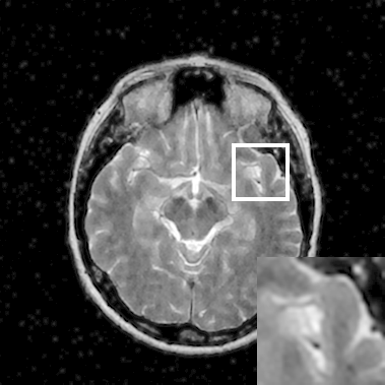

Figure 7: Reconstruction results for 20% variable density sampling. (a) Original. (b)-(h) Reconstructed images. (i)-(n) The errors of six CSMRI methods.

As shown in Figs. 7, 8 and 9, Sparse MRI and DLMRI have a lot of unpleasant artifacts, Residual learning and U-net can eliminate most of artifacts, but are not ideal for restoring image details. However, the proposed method can reconstruct better MR images, which outperforms other competitive methods in visualization of structures reconstruction and artifacts removal. Meanwhile, we can see from the absolute error residuals for three sampling experiments that the proposed MDN algorithm restores a finer detail structure than other algorithms. Moreover, we present the PSNR and SSIM values in Table I for different algorithms, sampling masks and sampling rates. It is demonstrated that the proposed method provides better reconstruction performance and visual results than other competitive methods. We can also see the obvious improvement of all algorithms over zero-filling both in visualization. In particular, a higher SSIM value of Sparse MRI appears when using 30% variable density random sampling, however, Sparse MRI generates more artifacts than the proposed MDN.